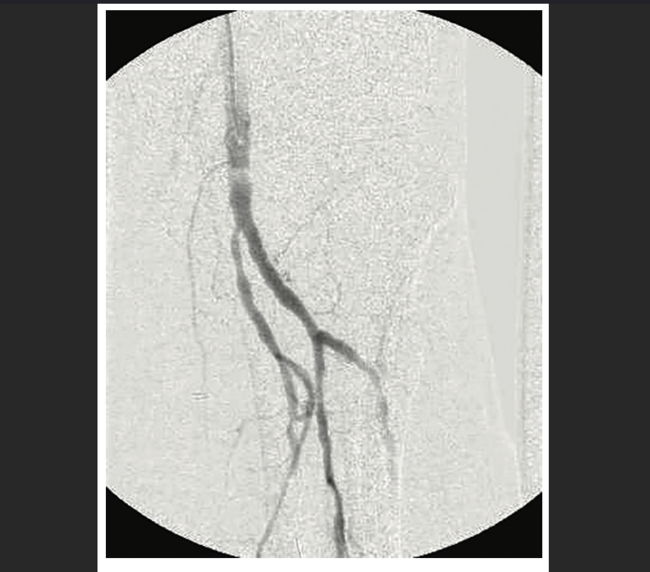

The treatment of chronic total occlusions (CTOs) poses a technical challenge for endovascular revascularization in both the coronary and peripheral arteries. Yet there has been significant progress made in the collective technical understanding of how to treat patients with an arterial CTO via endovascular methods.1,2 Experienced endovascular operators today have not only an armamentarium of catheters and wires and techniques to treat CTOs, but also a defined algorithm2 to escalate each as needed. For the treatment of peripheral vascular disease, when true lumen antegrade crossing of the occlusion fails, subintimal antegrade crossing can be attempted, typically by knuckling the wire in the subintimal plane and advancing to the end of the occlusion, termed STAR (Subintimal Tracking and Re-entry).3-5 However, crossing an occlusion through the subintimal plane in an antegrade fashion can have limited technical success, because it can often be difficult to re-enter the true lumen distal to the occlusion without resorting to use of a re-entry device.